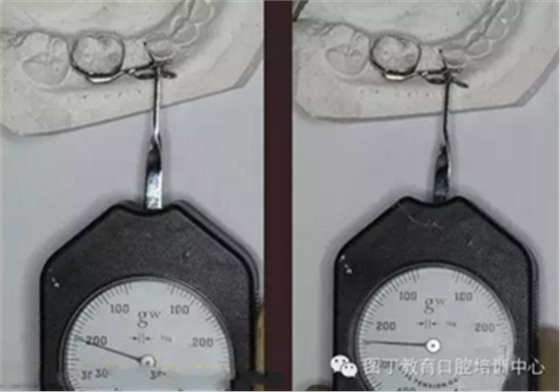

38、取下帶環(huán)、推簧加力

41、加力就位后測力值200~250克,初級力值偏大,隨著力的衰減力值維持在100~150g左右,直至間隙推開后,力值逐漸遞減為零,作為間隙保持器使用,等待恒牙萌出